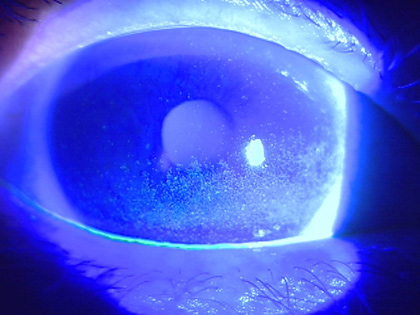

(2)細隙顕微鏡検査

細隙顕微鏡を使用し、フルオレセインという蛍光色素を用いて目の涙の量を見ることできます。また、角結膜の傷の状態を確認することができます。さらに、涙液層破壊時間(BUT)を測定することで、角膜表面にとどまりやすい涙か、そうでない涙かといった涙の質を評価することができます。